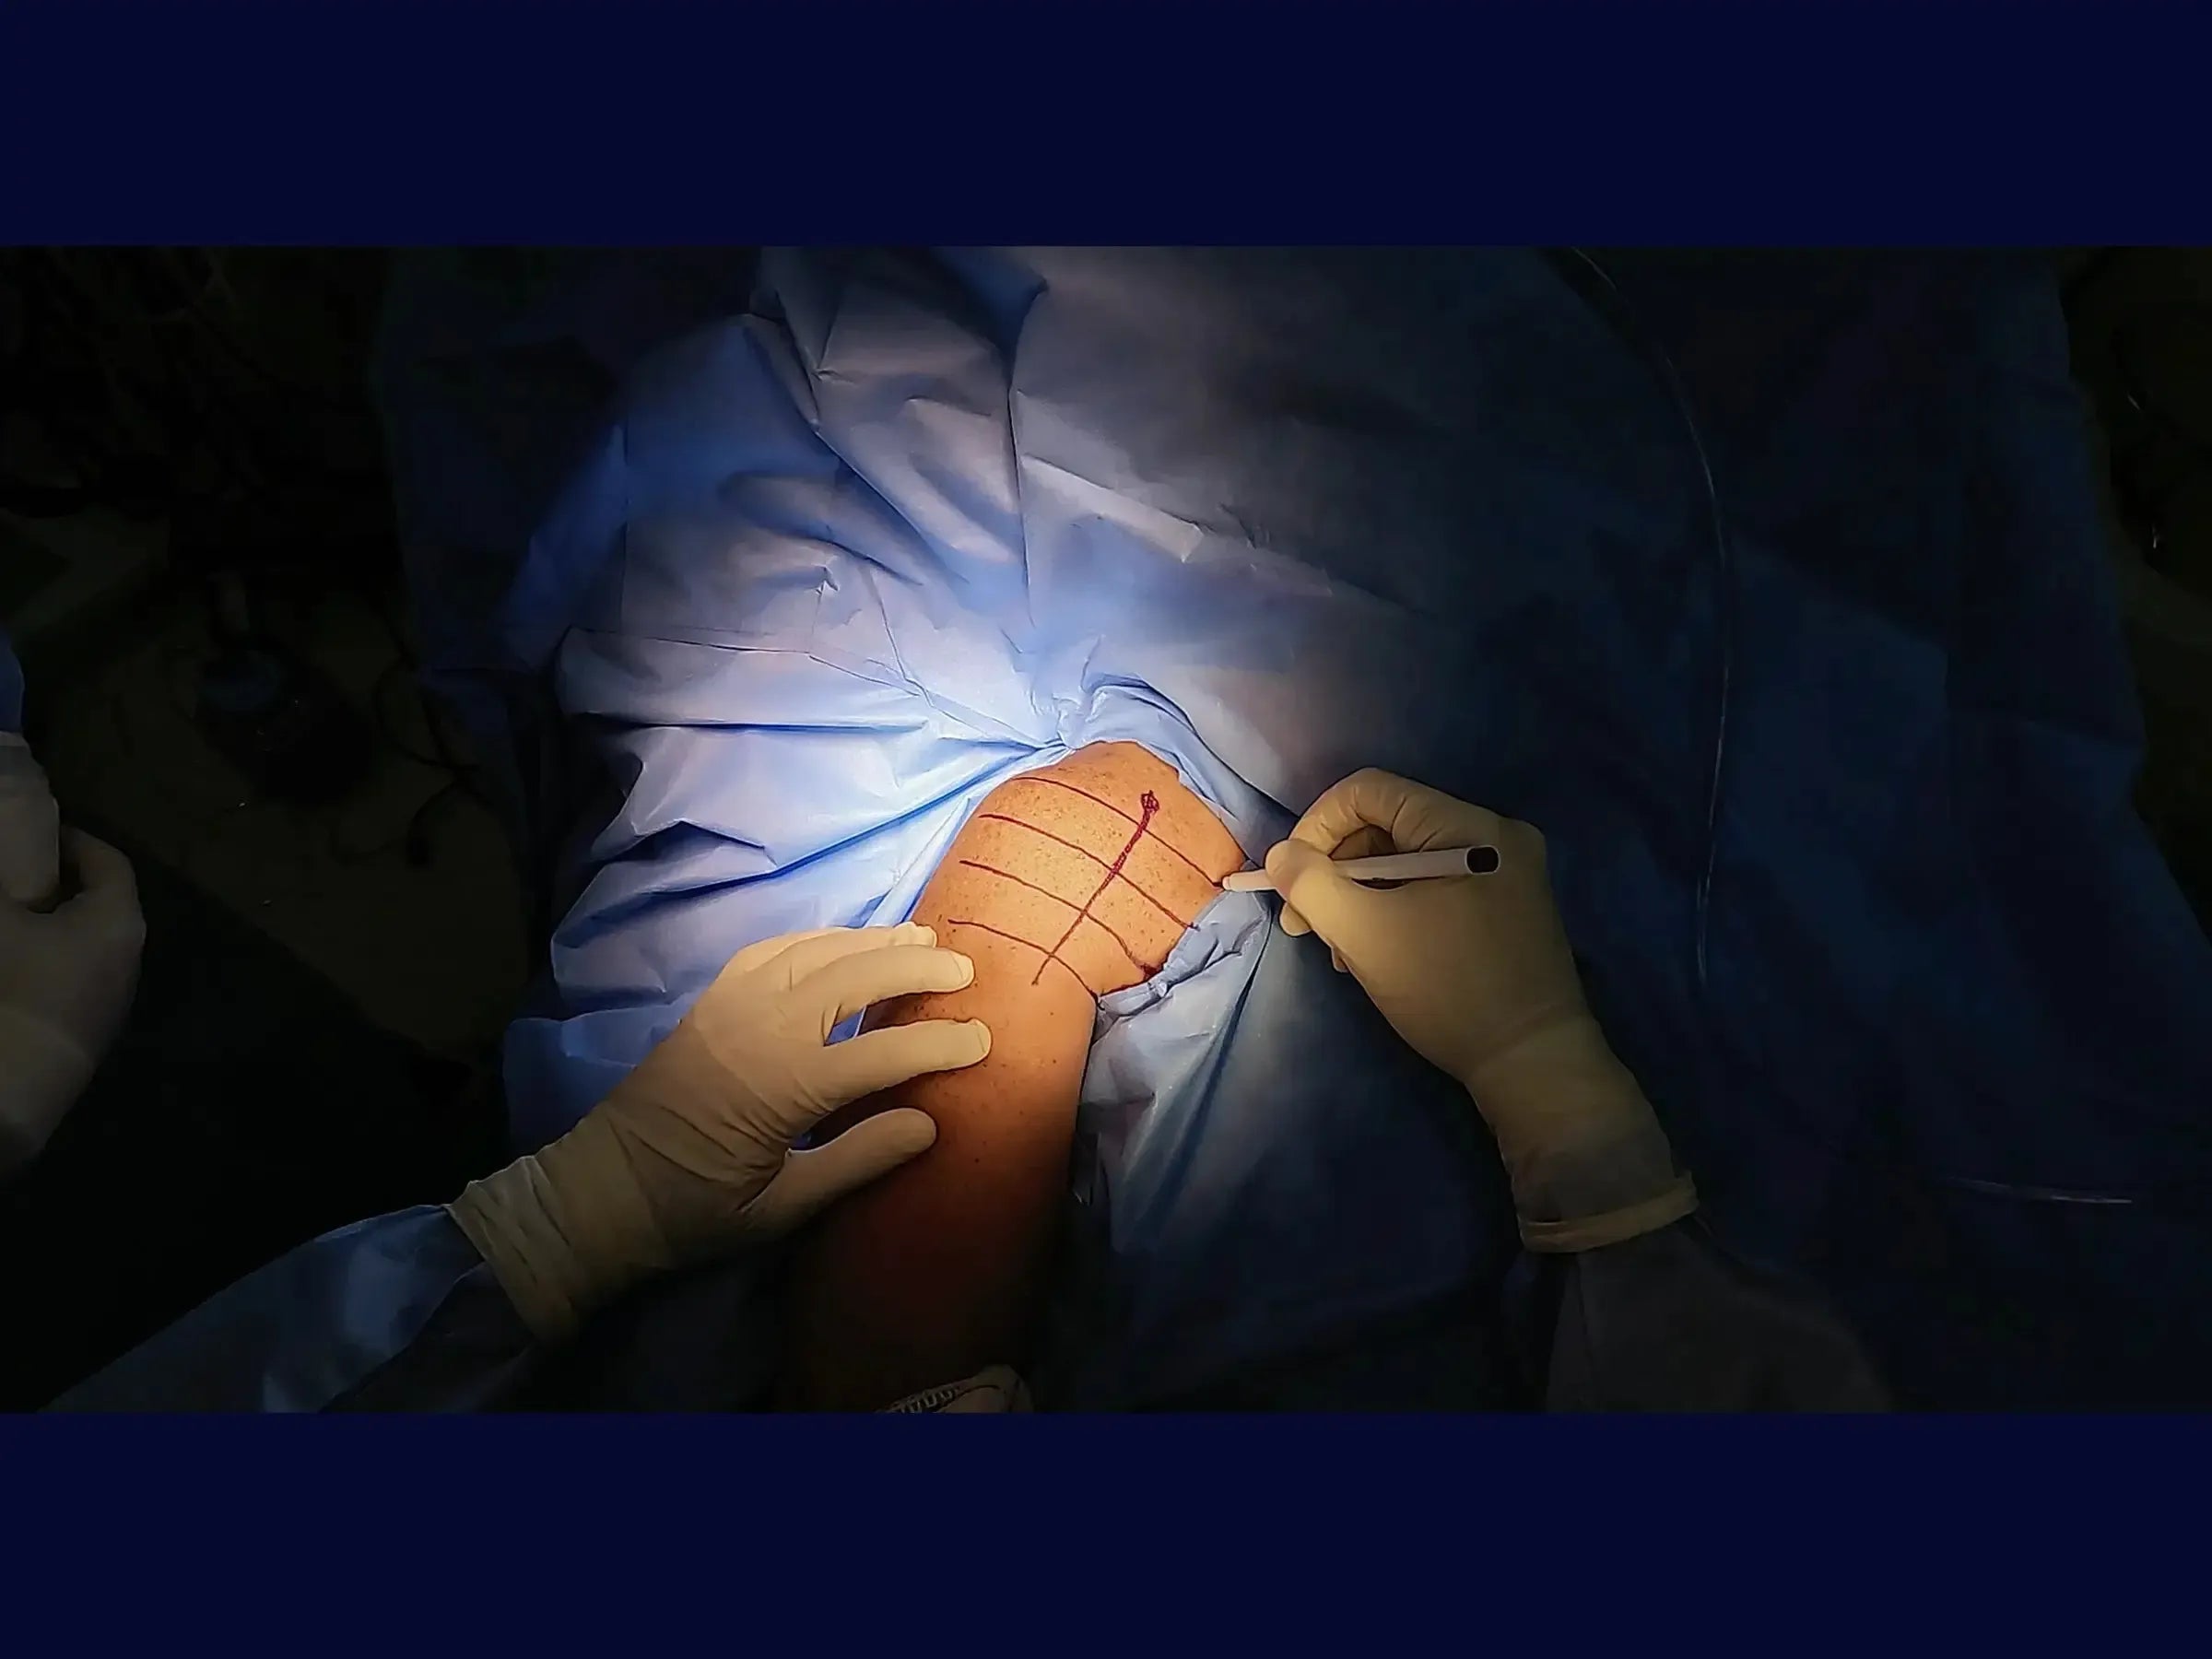

- Delimitação do Acesso Deltopeitoral: Técnicas de palpação do processo coracoide e identificação do intervalo deltopeitoral para um acesso cirúrgico preciso.

- Resultados Clínicos Superiores: Demonstração de resultados cirúrgicos com preservação da anatomia, acesso limpo sem agressão muscular e sutura estética.